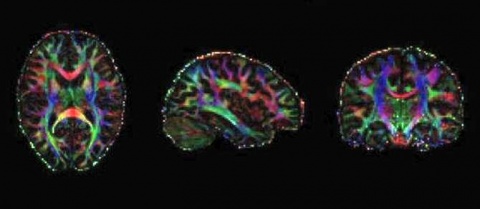

Un aspecto innovador de esta investigación es que sus autores emplearon una técnica llamada elastografía por resonancia magnética para medir de manera segura las propiedades mecánicas del tejido cerebral como indicación del grado de desarrollo del cerebro, en vez de emplear una técnica que activase esas dos regiones.

La elastografía por resonancia magnética es un método para obtener imágenes de las propiedades mecánicas de tejidos vivos mediante un escáner de resonancia magnética. En pocas palabras, los investigadores toman fotos de cómo el cerebro se deforma o se dobla al vibrar con bajas frecuencias, y luego procesan esas imágenes mediante un algoritmo específico para, en cierto modo, hacer “ingeniería inversa“ de lo que está sucediendo.

Las vibraciones de la elastografía por resonancia magnética no entrañan riesgos para todas las edades y proporcionan menos movimiento del que ocurre naturalmente en el cerebro. (Fuente: NCYT de Amazings)